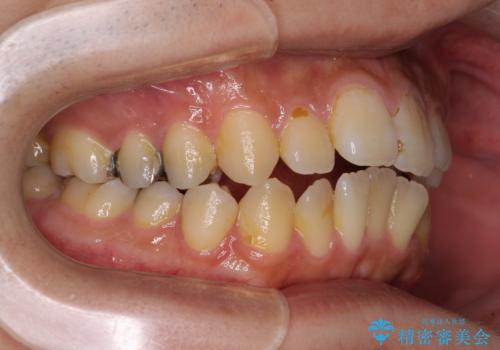

オープンバイトと目立つ銀歯 インビザライン矯正とセラミック修復治療

- 奥歯の目立つ銀歯と上下前歯の叢生と隙間を気にして来院された患者様です。

開咬の治療は、前歯を閉じるように動かすとともに、上下臼歯を圧下(骨内にめり込ませる)させることで進めて行きます。

インビザラインは臼歯の圧下を効果的に行えるため、インビザラインを用いて矯正治療を行うこととしました。

銀歯については、矯正治療により咬合関係を改善し、矯正治療後半に修復治療を行うこととしました。